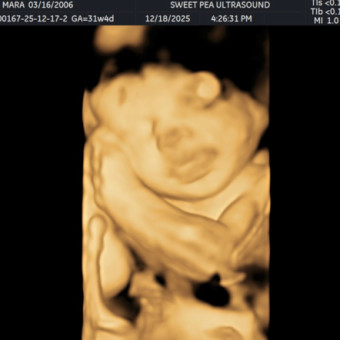

Ultrasounds🫶🏻